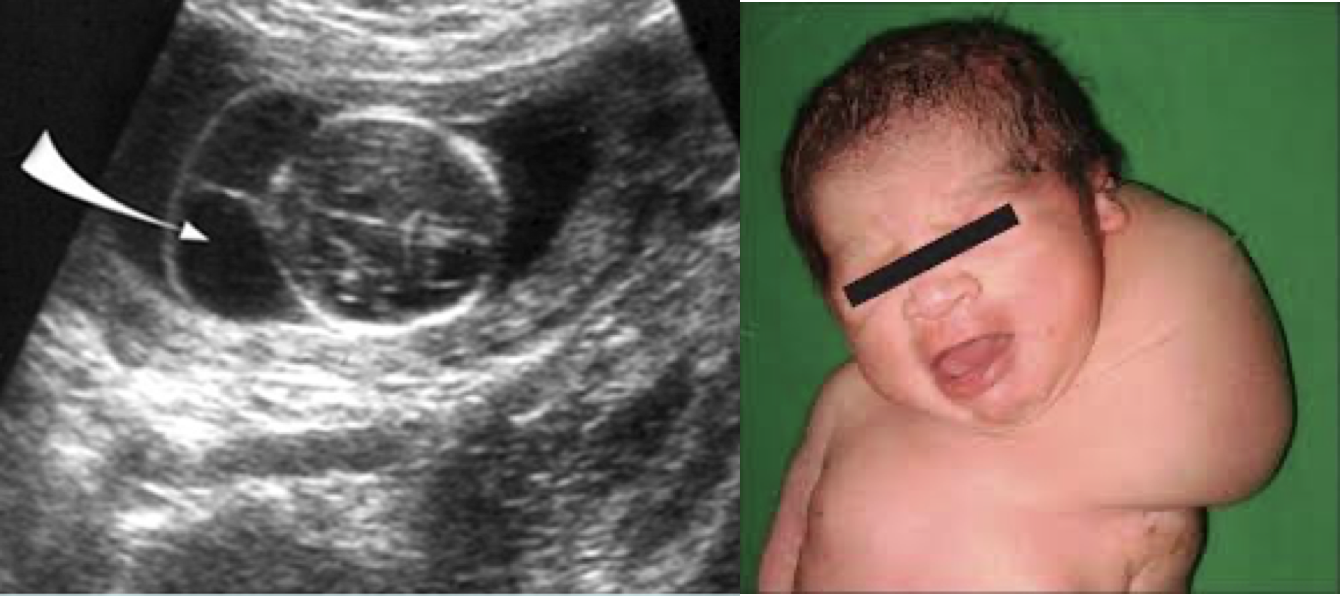

Cystic hygroma

• 정의 및 임상양상: Lymphangioma의 한 형태로, 경부 측면 부위에 발생하는 선천성 림프관 기형. 벽이 얇고 투명한 다방성 낭성 병변으로 림프액으로 차있음. 양측/편측 가능

• 연관 질환: 터너, 다운,누난, 에드워드 증후군 등의 염색체 이상, 태아 수종 (hydrops fetalis)

• 치료: 무증상이면서 병변이 작고 크기가 감소한다면 경과관찰, 증상이 있거나 진행성인 경우 수술적 절제 또는 경화요법. 기도압박시 기도확보 필요.